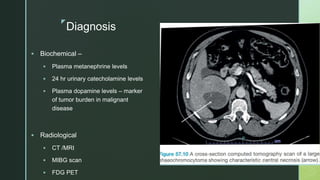

Diagnosis

 Biochemical –

 Plasma metanephrine levels

 24 hr urinary catecholamine levels

 Plasma dopamine levels – marker

of tumor burden in malignant

disease

 Radiological

 CT /MRI

 MIBG scan

 FDG PET